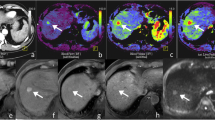

Model-free parameters and LLCR

No significant differences in model-free parameters (time to peak, time to washout) and maximal positive and negative LLCR were observed in HCCs between the two groups (all p = 0.054–0.398). Liver TTP and time to maximal negative LLCR were significantly longer with group 1 compared to group 2, due to delayed enhancement of the liver (Table 4, Fig. 3). There was no significant difference in the time to maximal positive LLCR between the two groups (p = 0.471) (Fig. 4).

Example of DCE-MRI enhancement curves of HCC (orange line) and liver parenchyma (blue line) in a 70-year-old male who received gadoxetate and a 63-year-old female who received Gd-BOPTA. Both HCCs show arterial phase hyperenhancement (a and c, peak enhancement indicated by the arrowhead on the enhancement curve) and washout (b and d, dashed circle on the enhancement curve). TTP, time to washout and time to maximal negative LLCR (asterisk on the enhancement curve) were 13.4, 66.3 and 142.1 s for gadoxetate; and 19.4, 67.8 and 154.1 s for Gd-BOPTA. Abbreviations: DCE-MRI, dynamic contrast-enhanced magnetic resonance imaging; HCC, hepatocellular carcinoma; LLCR, lesion-to-liver contrast ratio; Gd-BOPTA, gadobenate dimeglumine; AU, arbitrary units; s, seconds